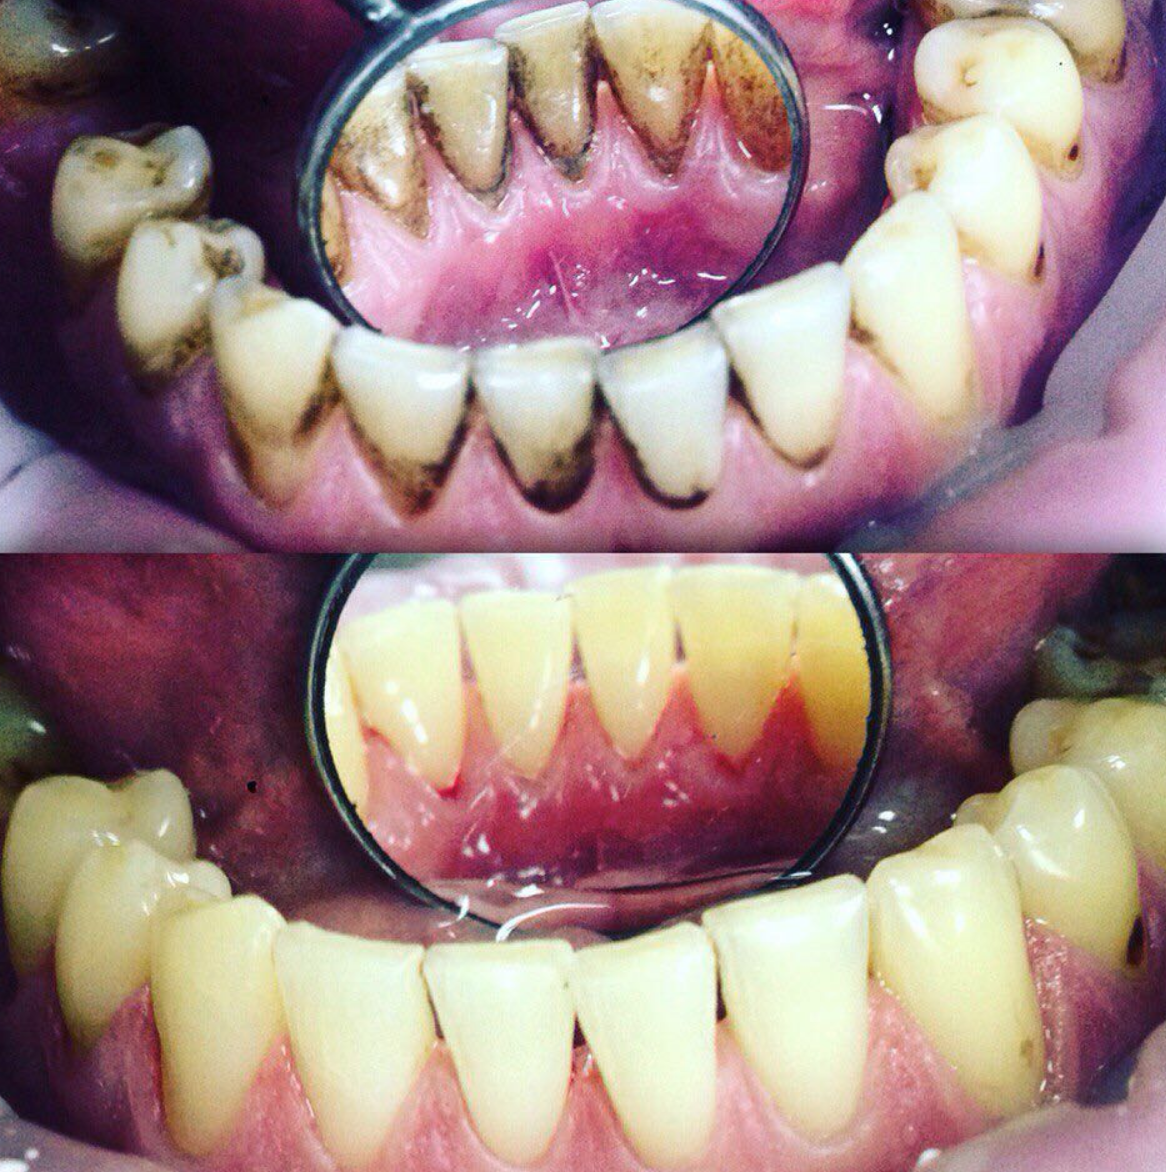

Убрать с эмали налёт и зубной камень

Снятие зубных отложений с помощью ультразвука

Твердые отложения (зубной камень) образуются в межзубных промежутках, на зубах в придесневой и поддесневой областях. Зубной камень может привести к развитию таких заболеваний, как гингивит, пародонтит или кариес. Процедуру проводят ультразвуковым скейлером, который с помощью вибраций удаляет твердые отложения с поверхности зуба.

Чистку делают с помощью ультразвукового скалера, который посылает вибрации на поверхность зуба. Такая технология безопасна и безболезненна. Это отличная альтернатива химическим или механическим способам снятия зубных отложений.

Удаление плотного налета, который образуется на зубах при плохой гигиене, вследствие курения или частого употребления чая или кофе проводится с помощью современной системы Air Flow. Специальный аппарат под давлением распыляет на зубы смесь воды и абразивных частиц. В наших клиниках используются самые щадящие порошки, чтобы не повредить поверхность эмали. Чистка Air Flow оказывает также осветляющий эффект — зубы становятся белее на один-два тона.